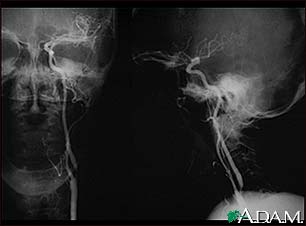

- Angiogram of the head to look for a blood vessel that is blocked or bleeding

- Magnetic resonance angiography (MRA) or CT angiography to check for abnormal blood vessels in the brain

- Endovascular thrombectomy may be needed. This is when a catheter is inserted into your arteries. Dye is injected while images of your brain’s blood vessels are reviewed. A clot, if found, could be removed through the catheter.